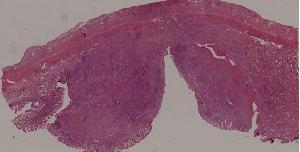

92.肠伤寒

低倍视野